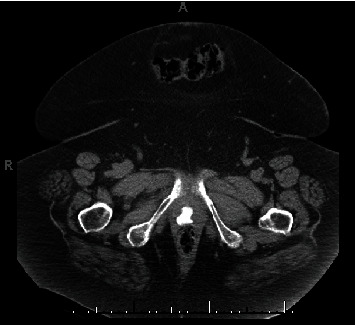

阴道结石是一种罕见的临床症状,可能在阴道尿液淤积的情况下出现。导致结石形成的因素有很多,结石的大小、位置和邻近结构的位置都会使处理变得复杂。一般来说,一旦确诊为阴道结石,应立即将其取出,并彻底评估周围的解剖结构,看是否有继发性瘘管、侵蚀或异物存在。本报告介绍了一例患有出血性膀胱炎的老年患者,其阴道结石形成于暴露的尿道中段吊带网片上。本报告强调了病理生理学、诊断因素和治疗方法。

The presence of a vaginal calculus is a rare clinical entity which may develop in the setting of vaginal urinary stagnation. Numerous factors contribute to stone formation, and management can be complicated by variations in size, location of the stone, and location of adjacent structures. Generally, once diagnosed, vaginal calculi should be removed and surrounding anatomy should be evaluated thoroughly for secondary fistula, erosion, or presence of an instituting foreign body. This report presents a case of vaginal calculus formation on exposed midurethral sling mesh in an elderly patient with hemorrhagic cystitis. This report emphasizes contributing pathophysiology, diagnostic factors, and treatment.